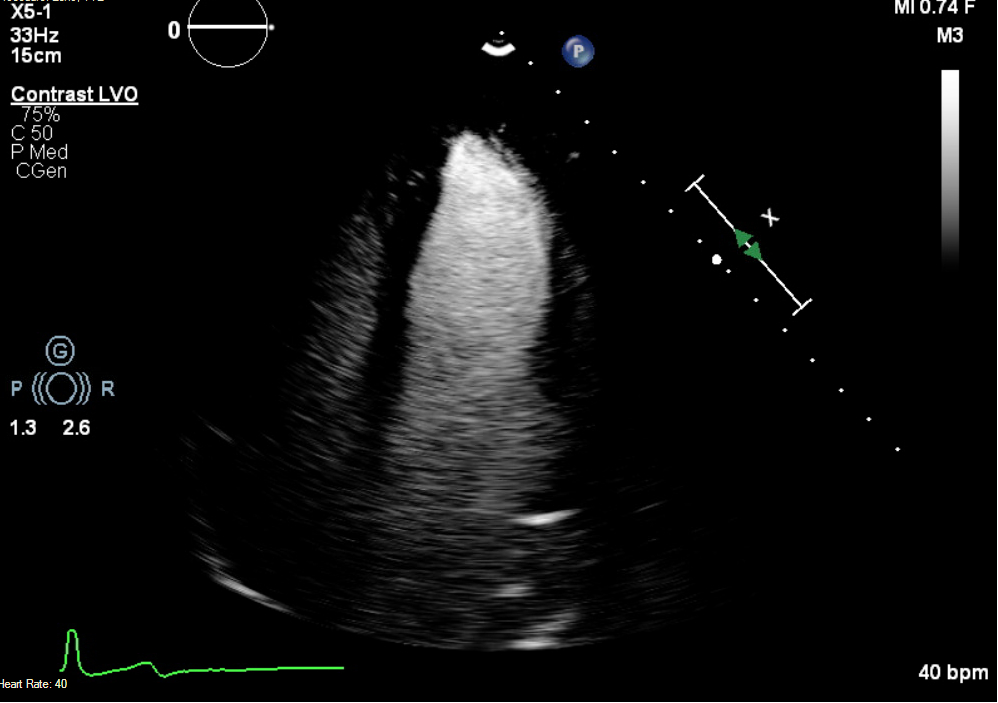

Case Presentation: A 20-year-old asymptomatic female with inferoseptal precordial T-wave inversions underwent sports pre-participation screening. Transthoracic echocardiography (TTE) revealed an apical LV crypt without hypertrophy. Cardiac MRI (CMR) demonstrated non-specific late gadolinium enhancement (LGE) in the basilar septum and inferior walls but no hypertrophy. Exercise stress testing and ambulatory monitoring were normal, and no activity restrictions were imposed. Repeat CMR at 2 years revealed new apical hypertrophy (12 mm) with apical to basal ratio of 1.2 raising suspicion for apical hypertrophy.